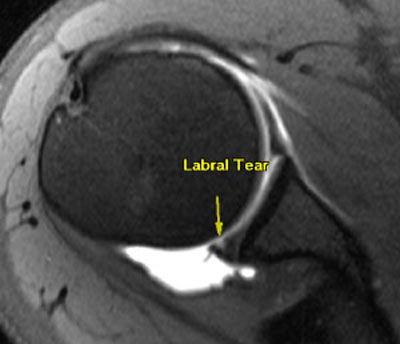

- Labral degeneration and labral tears

- Labral tears, SLAP Tears, Glenoid Labrum Tears, Shoulder Joint Tears

Please Note That Not All Patients will qualify for the treatment of degenerative Musculoskeletal conditions and shoulder injuries. Patients with injuries over 2-years-old, severely torn rotator cuffs &/or severe labrum damage may not be good candidates for treatment.Therapy Guidelines for Shoulder Injuries